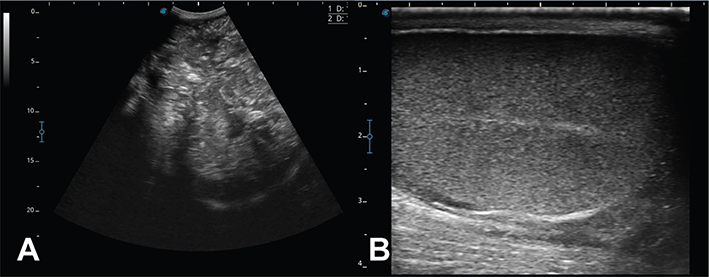

To facilitate ultrasonographic examination of the scrotums using a macro convex variable frequency (3-5 MHz) transducer on a portable ultrasound machine (Sonoscape X5, SonoScape Medical Corp, Centennial, CO), boars were sedated with intramuscular xylazine (0.3 mg/kg). Although the drug was extra label, it was used with owner’s consent in compliance with provision of the Animal Medicinal Drug Use Clarification Act of 1994 and 21 CFR 530. Additional restraint was provided with the use of sorting panels to create an enclosed area and then boars were placed in dorsal recumbency. Intrascrotal structures measured ~ 19 cm in diameter, exhibited a heterogeneous and mixed echogenic pattern with minimal cavitation, and had no defining features of a normal testis (Figure 3). In both boars the left testis was retained and could not be located ultrasonographically.

Figure 3.Figure 3. Boar 1: A. Sagittal plane ultrasonogram of scrotal mass; note heterogeneous complex echo pattern without obvious characteristics of normal testicular tissue and minimal cavitations (~ 19 cm in diameter). Unrelated animal: B. Sagittal plane ultrasound image of normal testicular parenchyma; note homogenous parenchyma with hyperechoic mediastinum (rete testes) (scale bar on left is in cm)